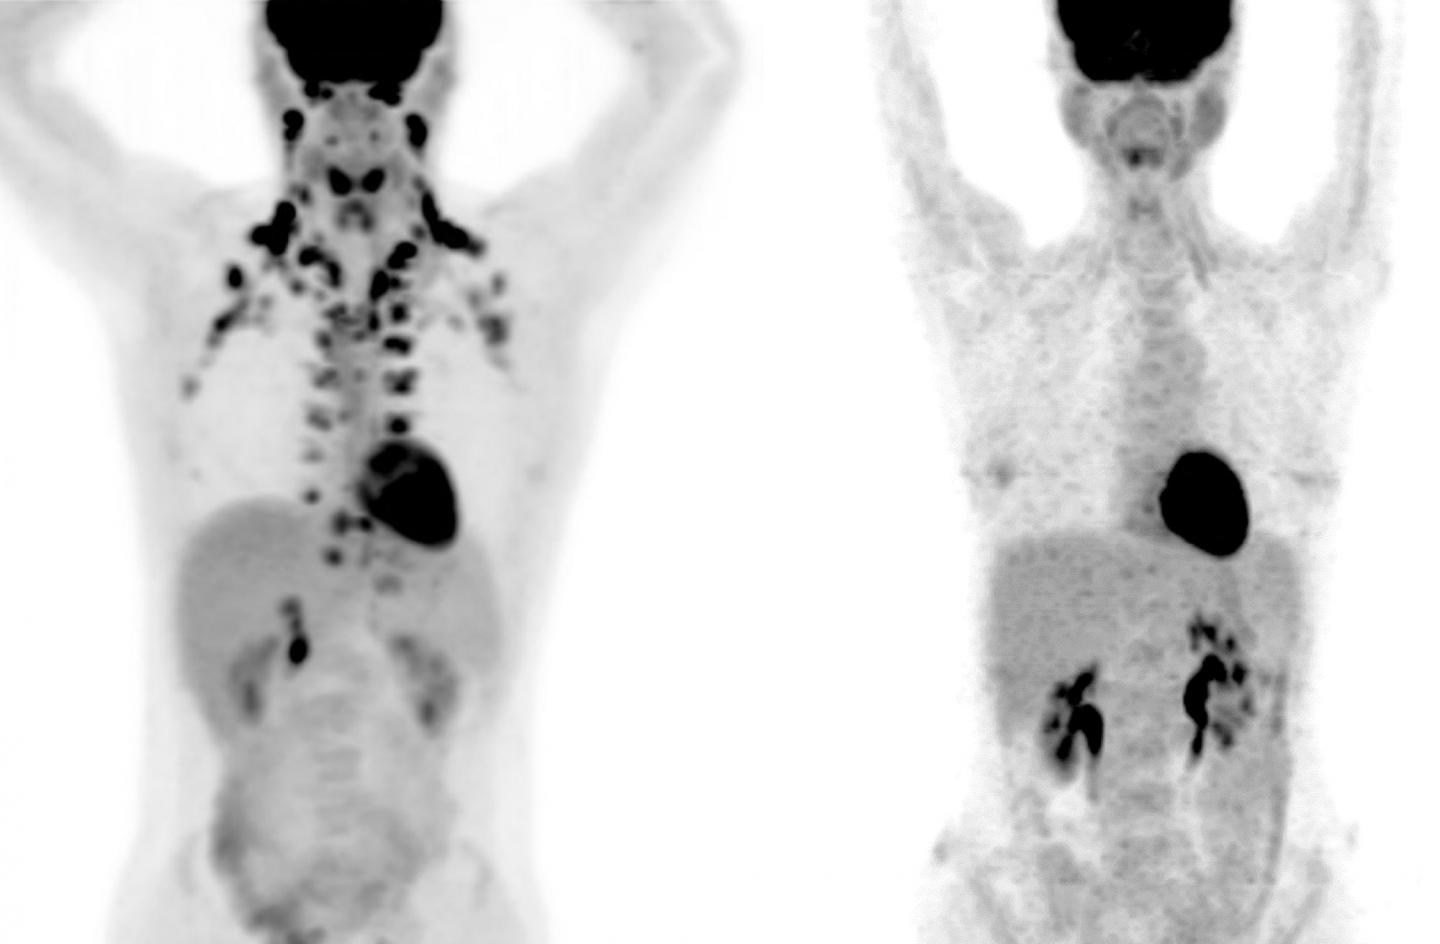

image: In these PET scans, the person on the left has abundant brown fat around the neck and cervical spine. The person on the right has no detectable brown fat.

Courtesy of MSKCC radiologists Andreas G. Wibmer and Heiko Schöder.

Large-scale studies of brown fat, however, have been practically impossible because this tissue shows up only on PET scans, a special type of medical imaging. "These scans are expensive, but more importantly, they use radiation," says Tobias Becher, the study's first author and formerly a Clinical Scholar in Cohen's lab. "We don't want to subject many healthy people to that."

In collaboration with Heiko Schoder and Andreas Wibmer at Memorial Sloan Kettering, the researchers reviewed 130,000 PET scans from more than 52,000 patients, and found the presence of brown fat in nearly 10 percent of individuals. (Cohen notes that this figure is likely an underestimate because the patients had been instructed to avoid cold exposure, exercise, and caffeine, all of which are thought to increase brown fat activity).